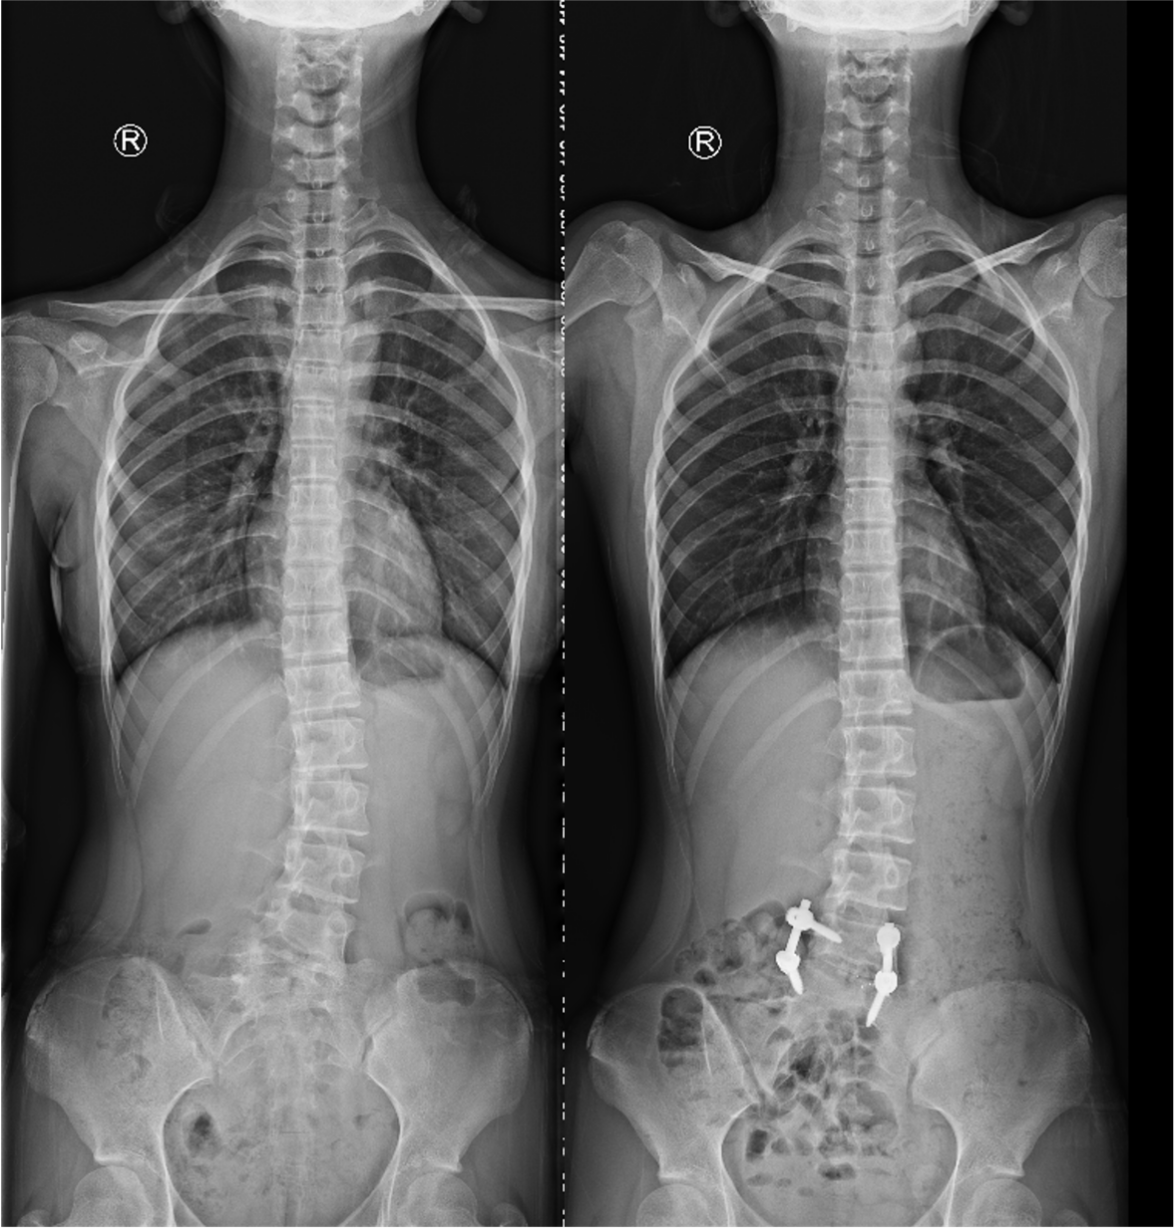

姜主任为小姑娘做了详细的体格检查,仔细阅读了影像资料后告知小王的父亲,孩子患的是一种第5腰椎先天性半椎体畸形而导致的腰椎侧弯畸形,采取手术方式干预迫在眉睫,否则畸形将会进一步加重。患者家属之前听说这种矫形手术切口很大,还需要打上十几个钉子,一直十分犹豫。看着患者父亲那焦急的神情,姜主任笑着安慰道:我们只需要采用相对小的手术把半椎体切除,再做适当的矫形即可。其余的部分畸形会随着生长发育自行矫正。在姜主任的耐心解释下,家属悬着的心终于放了下来,办理住院登记手续后不久顺利入院骨科病房。

入院进一步完善各项检查后,姜为民主任再一次对小王的影像资料进行了全面的研究,同时与团队成员商讨制定详细的手术方案。计划首先经后路切除L5半椎体,然后行椎间盘摘除凹侧椎间隙撑开矫形,再置入融合器行椎间融合,最后行短节段椎弓根内固定,以尽可能小的代价取得较为理想的效果。手术当日,姜主任熟练的通过截骨、置钉、撑开矫形、植骨融合等操作,顺利完成了手术。术后,患者小王恢复良好,术后影像检查显示半椎体已完全切除,矫形效果满意,手术非常成功。